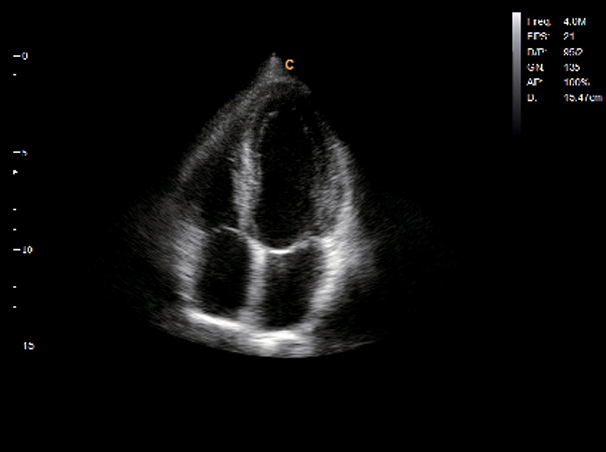

Cardiac

Apical Four Chamber View, B Mode